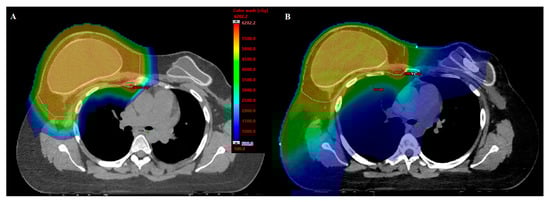

- MacDonald, S.M.; Jimenez, R.; Paetzold, P.; Adams, J.; Beatty, J.; DeLaney, T.F.; Kooy, H.; Taghian, A.G.; Lu, H.M. Proton radiotherapy for chest wall and regional lymphatic radiation; dose comparisons and treatment delivery. Radiat. Oncol. 2013, 8, 71. [Google Scholar] [CrossRef] [PubMed]

- Fagundes, M.; Hug, E.B.; Pankuch, M.; Fang, C.; McNeeley, S.; Mao, L.; Lavilla, M.; Schmidt, S.L.; Ward, C.; Cahlon, O.; et al. Proton Therapy for Local-regionally Advanced Breast Cancer Maximizes Cardiac Sparing. Int. J. Part. Ther. 2015, 1, 827–844. [Google Scholar] [CrossRef]